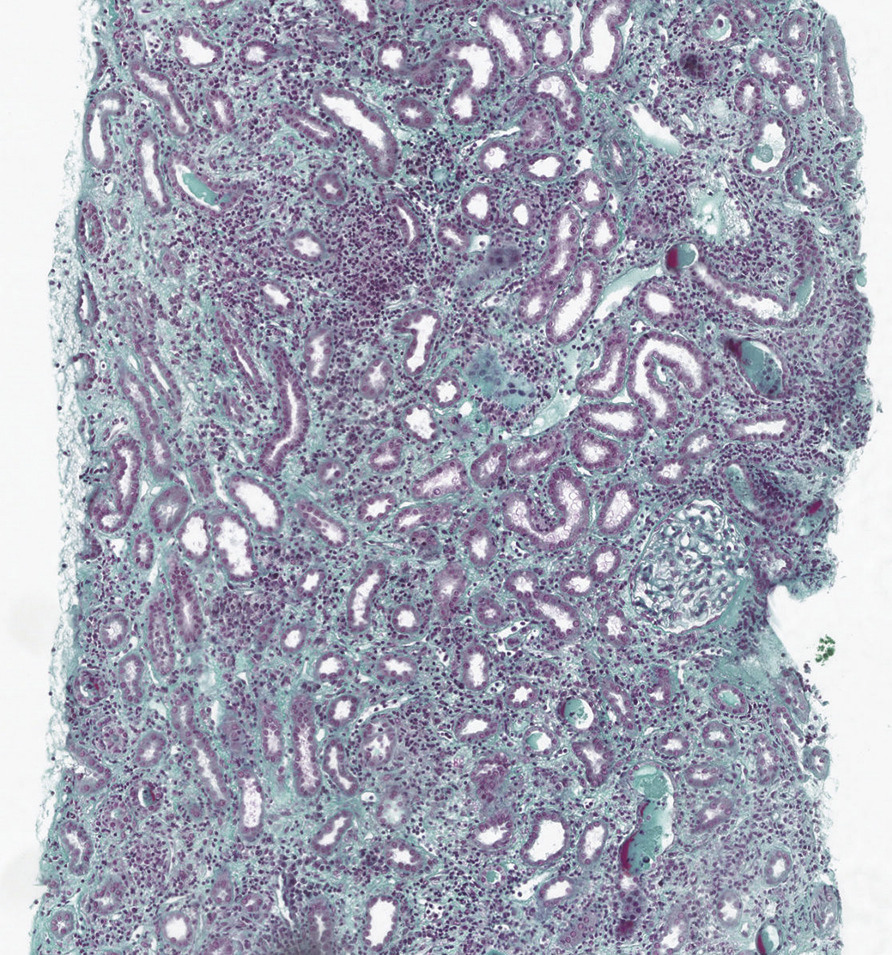

Les néphropathies interstitielles aiguës représentent une cause fréquente d’insuffisance rénale aiguë, dont la prévalence est probablement sous-estimée. Elles sont définies par la présence de lésions histologiques touchant essentiellement l’interstitium du parenchyme rénal, même si l’atteinte des tubules est souvent associée. Ces lésions, associant infiltration inflammatoire et œdème interstitiel, se traduisent par une détérioration de la fonction rénale, peu bruyante et évoluant à bas bruit, pouvant évoluer vers la néphropathie interstitielle chronique. Le diagnostic de certitude de la néphropathie interstitielle aiguë nécessite par définition la réalisation d’une biopsie rénale ; néanmoins, il est souvent évoqué devant un tableau clinico-biologique fortement évocateur, et la confirmation histologique est souvent absente. De ce fait, l’incidence précise de cette pathologie est difficile à préciser. En se fondant sur des séries rétrospectives, le diagnostic de néphropathie tubulo-interstitielle aiguë est retenu dans 1 à 5 % des examens histologiques rénaux en général et dans 10 à 35 % des biopsies réalisées dans un contexte d’insuffisance rénale aiguë.1

Néphropathies interstitielles aiguës immuno-allergiques

Elles sont secondaires à une réaction immunitaire déclenchée par un médicament, aboutissant à une infiltration du tissu interstitiel par des cellules mononucléées. Cliniquement, elles se caractérisent par la survenue fréquente, mais inconstante, de signes extrarénaux tels qu’une fièvre (30 %), une éruption cutanée maculopapulaire (21 %), des arthralgies (45 %), une hépatite aiguë, une hyperéosinophilie (25 %).2 Une douleur lombaire est parfois notée (20 %), sans autre signe fonctionnel urinaire. L’intervalle séparant l’introduction du médicament de la survenue de la néphropathie est variable, habituellement 8-10 jours. Les médicaments les plus fréquemment associés à cette pathologie sont les antibiotiques (bêtalactamines, fluoroquinolones, rifampicine), les inhibiteurs de la pompe à protons, les anti-inflammatoires non stéroïdiens (AINS), l’allopurinol, l’acide 5-aminosalicylique (5-ASA). L’histologie rénale montre un infiltrat inflammatoire mononucléé, associé à un œdème et parfois une fibrose interstitielle avec atrophie tubulaire. Ces cellules sont habituellement des lymphocytes T et des monocytes, mais on peut trouver des polynucléaires, des macrophages, voire de réels granulomes.Le traitement repose sur l’éviction du médicament néphrotoxique, mais aussi sur l’instauration d’une corticothérapie précoce.3 Même si aucun essai n’a étudié de façon contrôlée la dose et la durée optimales, on recommande une corticothérapie initiale entre 0,5 et 1 mg/kg/j de prednisone, avec une diminution rapide et un arrêt après 6 à 8 semaines.

Les néphropathies tubulo-interstitielles aiguës sont des pathologies dont le tableau est varié, allant de l’insuffisance rénale modérée à l’anurie complète, avec atteinte systémique touchant plusieurs organes, à l’insuffisance rénale aiguë nue, de découverte parfois fortuite. Les causes sont multiples et le bilan causal nécessite une enquête clinique et biologique approfondie et souvent la réalisation d’une biopsie rénale. La prise en charge conduit souvent à une corticothérapie, associée au traitement spécifique (arrêt des médicaments néphrotoxiques, traitement anti-infectieux dans les causes bactériennes ou virales, chimiothérapie dans les causes néoplasiques ou la néphropathie à cylindres myélomateux). Même si la récupération de la fonction rénale est usuelle, les séquelles peuvent être significatives, avec le développement d’une fibrose interstitielle et d’une atrophie tubulaire qui peut avoir des conséquences fonctionnelles, surtout en cas de répétition des épisodes.

La néphropathie interstitielle aiguë représente 10 à 30 % des insuffisances rénales aiguës organiques documentées histologiquement. Elle est caractérisée par une infiltration de l’interstitium rénal par des cellules inflammatoires, aboutissant à un œdème, des lésions tubulaires et une évolution vers la fibrose. Les causes sont multiples, d’origine médicamenteuse (par toxicité directe ou mécanisme immuno-allergique), toxique, infectieuse, auto-immune ou néoplasique. Les signes extrarénaux sont souvent absents, la protéinurie est tubulaire et de faible débit, associée à une leucocyturie fréquente. Le traitement repose souvent sur une corticothérapie, associée au traitement spécifique : arrêt des médicaments néphrotoxiques, traitement anti-infectieux dans les causes bactériennes ou virales, chimiothérapie dans les cancers